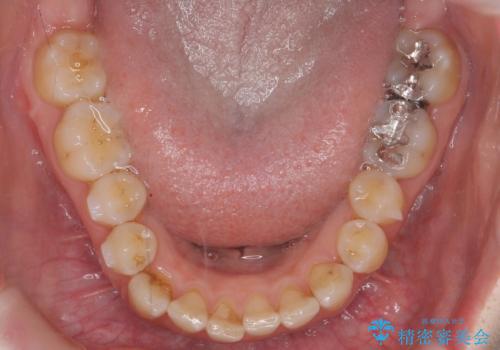

- 前歯のがたつきとガミースマイルの改善を希望して来院。

ガミーは非常に軽度でひどくはなかったのですが、改善を強く希望されていました。

上の前歯をひっぱりあげて目立たなくするために、上の前歯のワイヤー部分矯正を行い、ミニスクリューからわずかに引っ張り上げました。

また、右上の犬歯の反対咬合についてもワイヤー矯正で短期間で改善することができました。

前歯の過蓋咬合についても改善しています。